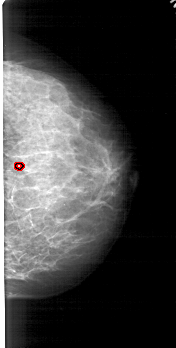

A_1794_1.RIGHT_CC

RIGHT_CC LINES 4861 PIXELS_PER_LINE 2461 BITS_PER_PIXEL 12 RESOLUTION 43.5 OVERLAY

FILE: A_1794_1.RIGHT_CC.OVERLAY

TOTAL_ABNORMALITIES 1

ABNORMALITY 1

LESION_TYPE CALCIFICATION TYPE PUNCTATE DISTRIBUTION CLUSTERED

ASSESSMENT 4

SUBTLETY 1

PATHOLOGY BENIGN

TOTAL_OUTLINES 1

BOUNDARY